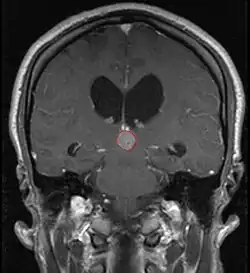

Radiation Oncology/CNS/Pineal

Pineal Gland Tumors

• Work-up includes MRI, CSF, serum markers for bHCG and AFP